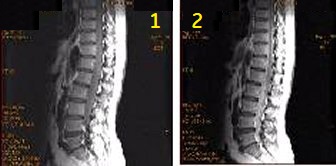

| 1 | FSE scan time 4:17, TR = 1833, Eff TE = 12 |

| 2 | FRFSE scan time = 4:29, TR = 1917, Eff TE = 12 |